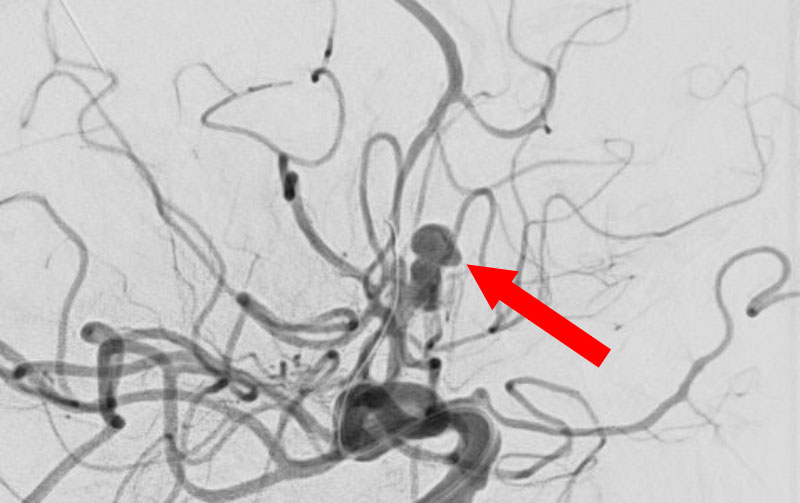

'25年11月

左内頚動脈脳動脈瘤

60代

大阪府の病院

No.1595 手術前

No.1595 手術中

No.1595 手術後